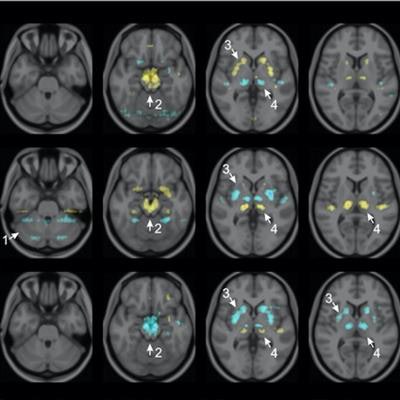

Visualization of average saliency maps of patients with idiopathic Parkinson's disease (IPD), multiple system atrophy (MSA), and progressive supranuclear palsy (PSP) in the training cohort showing characteristic regions contributing to the deep metabolic imaging (DMI) indices. The color corresponds to the importance score indicating the contribution of a region for the generated DMI indices. The color directions (yellow and red vs. cyan and blue) represent different influences on the DMI indices (increased uptake value contributes to the increase or decrease of the probability of IPD, MSA, or PSP in the DMI indices). The arrows pointed to the most salient brain regions including 1: Cerebellum, 2: Midbrain, 3: Putamen, and 4: Thalamus. Image courtesy of the Journal of Nuclear Medicine.

Visualization of average saliency maps of patients with idiopathic Parkinson's disease (IPD), multiple system atrophy (MSA), and progressive supranuclear palsy (PSP) in the training cohort showing characteristic regions contributing to the deep metabolic imaging (DMI) indices. The color corresponds to the importance score indicating the contribution of a region for the generated DMI indices. The color directions (yellow and red vs. cyan and blue) represent different influences on the DMI indices (increased uptake value contributes to the increase or decrease of the probability of IPD, MSA, or PSP in the DMI indices). The arrows pointed to the most salient brain regions including 1: Cerebellum, 2: Midbrain, 3: Putamen, and 4: Thalamus. Image courtesy of the Journal of Nuclear Medicine.The deep metabolic imaging indices extracted from PDD-Net provided an early and accurate method for the differential diagnosis of parkinsonian syndromes, with high rates of sensitivity and specificity for Parkinson's disease, multiple system atrophy, and progressive supranuclear palsy, according to the findings.